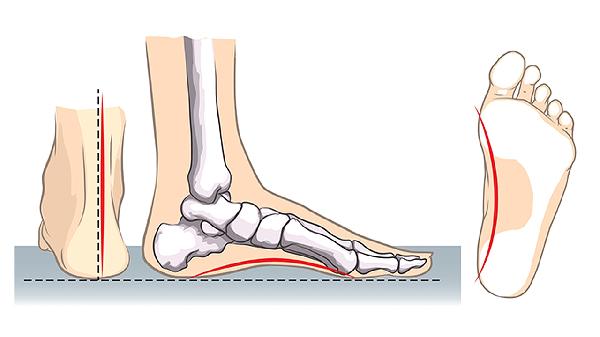

脊柱侧弯或驼背会使身高缩水2-3厘米。通过靠墙站立训练、普拉提核心强化、专业形体矫正课程,可改善椎间隙压缩状态。每日进行10分钟猫牛式伸展、悬吊单杠放松脊椎,长期坚持能恢复部分隐匿身高。

跳绳、篮球摸高、游泳等冲击性运动可刺激关节软骨代谢。每周3次以上30分钟跳跃训练,配合游泳时的水体牵引力,有助于维持椎间盘含水量。瑜伽中的山式、树式等拉伸动作也能优化身体线条。